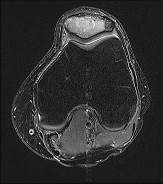

Figures 96a and 96b are the MRI sections of the symptomatic left knee of a 28-year-old man with left anterior knee pain 18 months after undergoing an allogenic bone marrow transplant for acute myelogenous leukemia. His intraoperative fluoroscopy images are shown in Figures 96c and 96d. What is most critical when obtaining a diagnosis for this patient?